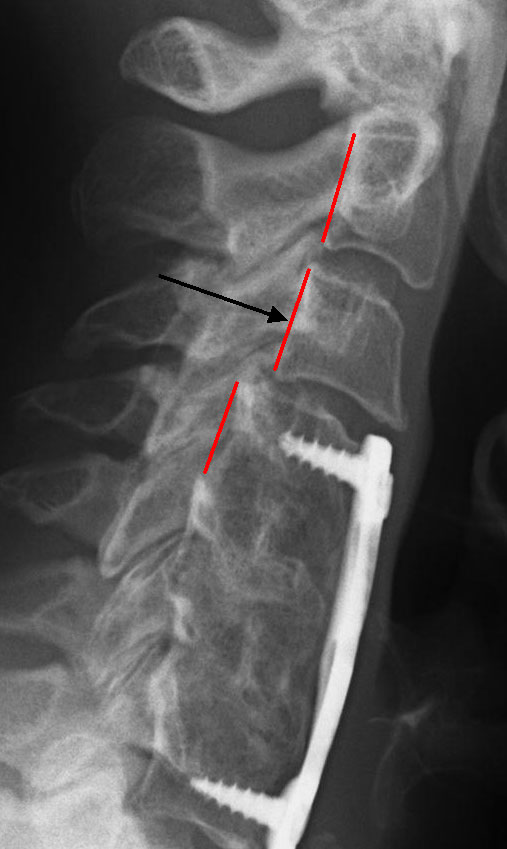

Therefore spinal hardware eg. One of the best signs for pseudoarthrosis failed fusion is a halo formation on the x-ray or CT scan. Finally how well does it work to try a different approach when treating failed fusions.

If there is an issue with your implanted spine hardware your physician will first confirm with an x-ray or other imaging scan. The cause of failed cervical fusion surgery can vary considerably with possibilities that include. If the fusion doesnt happen as it should pseudoarthrosis the screws can loosen.

Pedicle screws may be used as an internal splint to hold the spine while it fuses after spine surgery.